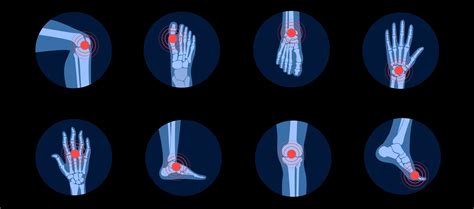

Weblet's discuss effective strategies for managing rheumatoid arthritis pain. It emphasizes a comprehensive approach, including regular physical activity, medication. Webby focusing on pain management, improved mobility, and muscle strengthening, physiotherapy can help you reclaim your life and manage arthritis more effectively.